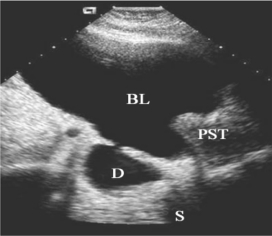

图30-5 膀胱憩室声像图

BL:膀胱;PST:前列腺;D:憩室;S:脊柱

1.膀胱后方及侧方见膀胱壁外有一个或数个圆形或椭圆形的无回声区,壁薄而光滑,颇似囊肿。

2.憩室与膀胱相通,可显示憩室口或排尿后憩室腔缩小(图30-5)。